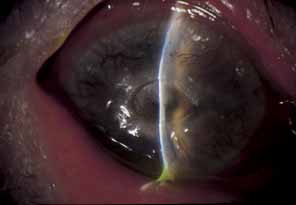

IRIS AND UVEA.

HZO can cause either a nongranulomatous or granulomatous iridocyclitis (anterior uveitis) with extensive keratic precipitates and posterior synechiae.69 The iridocyclitis tends to be chronic and recurrent and may require long-term, carefully titrated topical corticosteroids for control. Anterior uveal involvement can occur independent of corneal disease and is heralded by blurred vision, intense photophobia, ciliary injection, edema of the iris, hyperemia, miosis, and inflammatory anterior chamber cells and protein flare.62 A severe “plastic” iridocyclitis, with hypopyon, hyphema, and intractable secondary glaucoma, can be observed (Fig. 16). As a result of chronic iridocyclitis, corneal edema secondary to endothelial damage and sectoral iris atrophy can occur.62 Endothelial cell loss is especially common with herpes zoster keratouveitis, even with normal intraocular pressure.64,65 Histopathologically, herpes zoster iritis is an ischemic, occlusive vasculitis. The typical sector iris atrophy that accompanies HZO is the result of focal ischemic necrosis (Fig. 17).70 In contrast, herpes simplex iritis is primarily a lymphocytic infiltration without ischemia, and causes a more diffuse iris atrophy.16,72,73

Fig. 16 Herpes zoster ophthalmicus. Corneal edema, abscess formation, and hypopyon iridocyclitis in an eye that was subsequently enucleated for intractable glaucoma and pain.

Fig. 17 Sectoral iris atrophy, status post–herpes zoster ophthalmicus. Note the moth-eaten appearance of iris in sectoral area, underlying a corresponding area of sclerokeratitis and limbal vascularization.